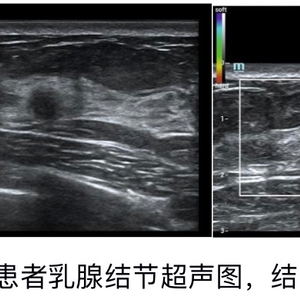

小吴是一位30多岁女性,一年半前体检超声发现自己双侧乳腺都有3类结节,结节大小均在1cm以内,咨询了医生后,给出的建议是每半年定期复查。小吴很认真的听从医生的建议,每6个月进行一次检查:第一次复查乳腺超声提示3类。6个月后她对自己很负责地再次来医院复查,由于有乳腺癌家族史,小吴比较焦虑,医生再和她充分沟通后建议她进行了乳腺超声和钼靶检查,结果仍提示是3类结节。两次复查结果结节没有明显长大,类别仍是3类,她自己也没有乳腺疼痛等任何不适,小吴很开心地认为自己的乳腺结节是安全的。又过了半年,小吴来医院做第三次复查,医生建议她再次进行了乳腺超声检查。检查中,其右侧乳腺内一个直径仅5mm的结节在灰阶超声和彩色多普勒的特征上没有明显的变化,但弹性超声提示肿块是高硬度的,诊断为BI-RADS 4a类。根据诊断分类,超声科医生建议患者对该小结节进行活检穿刺,最终得到病理结果:浸润性导管癌。所幸分期好、级别低、范围小,她可以进行保乳手术,创伤也比较小,无需化疗、仅需进行一段时间的内分泌治疗,预期的预后效果也比较好。小吴是幸运的,在连续三次影像学检查都说良性可能大的情况下,没有掉以轻心,而是谨遵医嘱,定期复查。最终早早地将“癌”这个可恶又极会隐藏的定时炸弹揪出来拆掉了,真是不幸中的万幸。

超声弹性究竟是什么?

我们知道不同物体的软硬度是不同的,在外界压力下会发生不同程度的变形,就像海绵软,受压后形变大,钢铁硬,受压后形变小,一般不是非常巨大的压力下,我们肉眼是看不出变形的。我们人体的组织也是会受压变形的,不同组织受压后会有不同的变形。一般来说恶性肿瘤发生的形变小于良性肿瘤。超声弹性就是利用这一特性,在常规超声的基础上对病灶区进行物理处理,得到病灶的形变系数,以彩色编码显示,来判别病变组织的弹性大小,从而推断某些病变的可能性。超声弹性是一种安全、无创、无辐射的检查方式,可进一步提升常规超声的准确度,因而被列入了BI-RADS 第五版的诊断指标中。